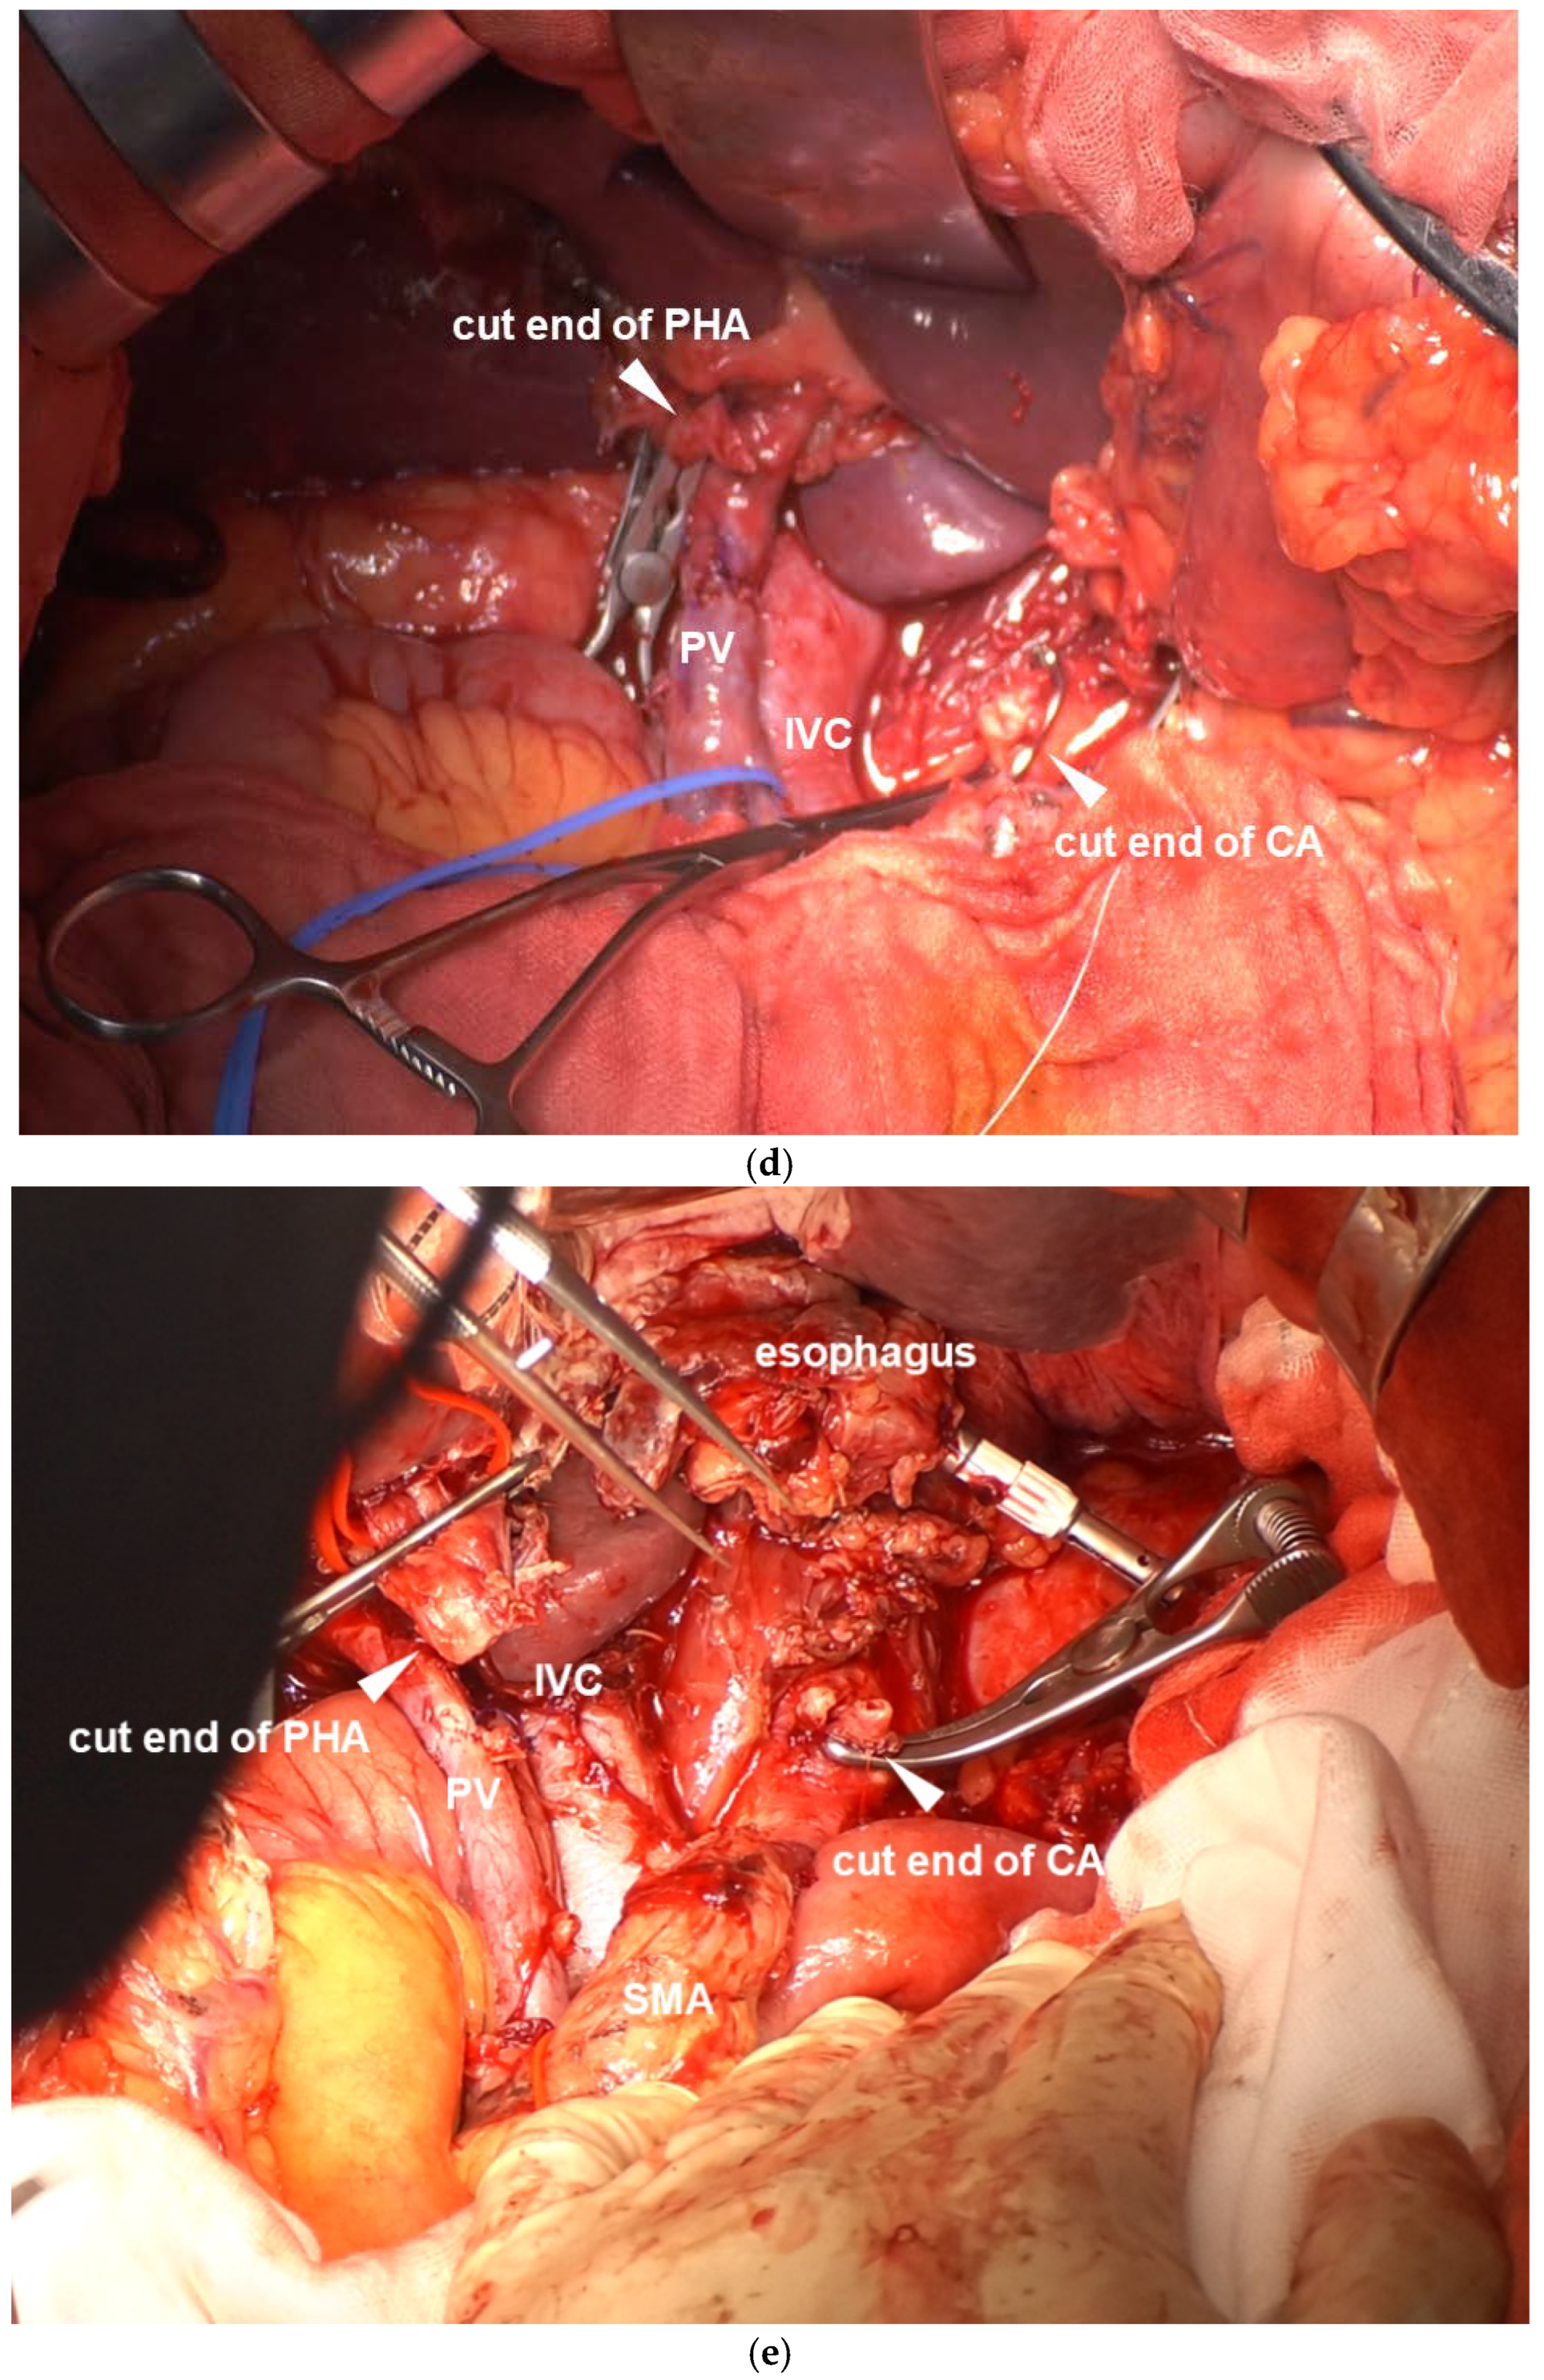

2.2.4. TP-CAR+TG

2.3. CA Resection and Reconstruction

CA Reconstruction in TP-CAR+TG